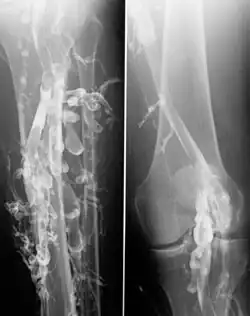

![]() Flebografía en un paciente con trombosis venosa profunda. | ||

La venografía de contraste es el estándar principal para diferenciar los métodos de diagnóstico por imágenes para la trombosis venosa profunda; aunque, debido a su costo, invasividad y otras limitaciones, esta prueba rara vez se realiza.[1]

La venografía también se puede utilizar para distinguir los coágulos de sangre de las obstrucciones en las venas, para evaluar los problemas congénitos en las venas, para ver cómo funcionan las válvulas profundas de las venas de las piernas o para identificar una vena para el injerto de derivación arterial.